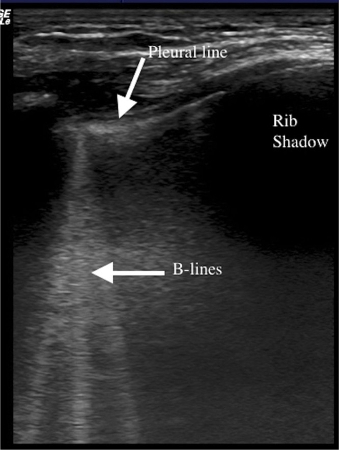

Lung ultrasonography scan of a single intercostal space showing B-lines (white vertical lines) - curved array

Wimalasena Y, Kocierz L, Strong D, et al. Lung ultrasound: a useful tool in the assessment of the dyspnoeic patient in the emergency department. Fact or fiction? Emerg Med J. 2017 Mar 3. pii.